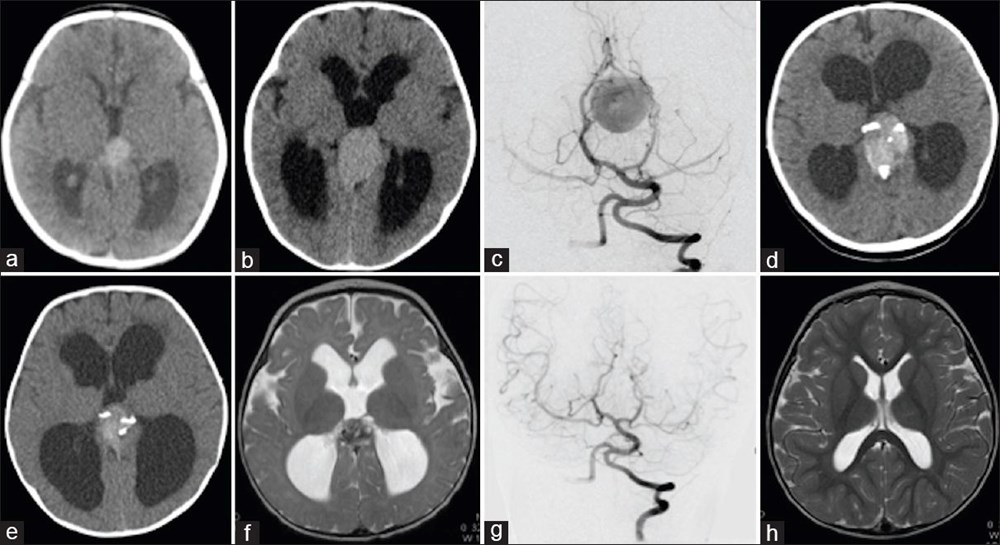

ABD'li doktorlar, türünün ilk örneği olan bir beyin ameliyatını çocuk henüz anne karnındayken gerçekleştirerek, doğmamış bir bebeği kesin ölümden kurtardı. Genetik bir bozukluk olan Galen damarı Malformasyonu'ndan (VOGM) muzdarip rahimdeki bebeğin kafatasını kesmeyi ve ardından gelişmekte olan beyni ameliyat etmeyi içeren titiz bir prosedür gerçekleştiren doktorlar, dünyada ilk kez yapılan operasyon ile birçok çocuğun hayatının kurtarılabileceğini müjdeledi.Türünün ilk örneği olan ve hayat kurtaran bir prosedürle anne karnındaki bir bebeğe beyin ameliyatı yapıldı.ABD'li doktorlar doğmamış çocuktaki ölümcül bir damar rahatsızlığını tedavi ederek doğumdan kısa bir süre sonra kalp yetmezliği ve felç geçirmesini önledi. Daha önce de rahimde beyin ameliyatı yapılmıştı, ancak Galen Damarı Malformasyonu (VOGM) adı verilen bu nadir hastalık için yapılmamıştı.Anneyi 34. haftada ameliyat eden bilim insanları, operasyonu yönlendirmek için ultrason kullandı. BEBEK SAĞLIKLI BİR ŞEKİLDE EVİNE DÖNDÜBoston Çocuk Hastanesi'nden Dr. Darren Orbach konuyla ilgili yaptığı açıklamada, "Genellikle doğumdan sonra görülen bebeğin sağlığındaki düşüşün ortaya çıkmadığını görmek bizi çok heyecanlandırdı. Şu anda altı haftalık olan bebeğin, ilaç kullanmadan, normal beslenerek ve kilo alarak eve döndüğünü bildirmekten memnuniyet duyuyoruz. Operasyonun beyin üzerinde herhangi bir olumsuz etki belirtisi yok." dedi. GALEN DAMAR FORMASYONU HAKKINDABununla birlikte, Galen Damar Malformasyonu (VOGM) her yıl yüzlerce bebeği etkiliyor ve çocuklar doğumun ilk birkaç gününden sonra hayatta kalamayabiliyor. Hastalık, beyindeki atardamarların kanı kılcal damarlar yerine doğrudan toplardamarlara akıtmasına neden olarak kalbin boğulmasına ve beyin hasarına yol açıyor.Mevcut tedaviler ise şimdiye kadar bebeğin doğumundan sonrası ile sınırlıydı, ancak bu noktada çoğu vakada beyin hasarı çoktan meydana gelmiş oluyordu. "Stroke" adlı bilimsel dergide sonuçları açıklanan yeni cerrahi operasyon, hastalığı bebeği etkilemeden önce iyileştirmeyi amaçlıyor.Diğer taraftan, operasyon kapsamında 10 sağlık görevlisinden oluşan bir ekip, annenin karnından uzun bir iğneyi bebeğin beyninin arterlerin etkilendiği kısmına yönlendirmek için ultrason kullandı. Doktorlar, daha sonra damarlara geri akışı engellemek için damar içine küçük bir madde enjekte etti.Dr. Orbach, "Bu yaklaşım, Galen Damarı Malformasyonu’nun tedavisinde büyük bir potansiyele sahip. Malformasyonu doğumdan önce onarıyoruz ve doğumdan sonra tersine çevirmeye çalışmak yerine kalp yetmezliğini ortaya çıkmadan önlüyoruz. Bu, bu bebekler arasında uzun vadeli beyin hasarı, sakatlık veya ölüm riskini önemli ölçüde azaltabilir." diye konuştu.